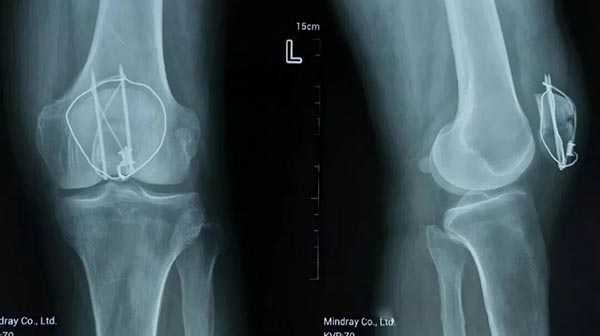

2024年12月11日,柳先生因左膝髌骨骨折在深圳接受切开复位张力带内固定术。然而术后4个月,他的左膝持续肿痛、活动受限,复查显示骨折断端分离、愈合不良。对于74岁高龄且合并基础疾病的柳先生而言,二次手术风险极高,保守治疗又效果甚微,患者及家属一度陷入焦虑。

2025年4月15日,经病友推荐,柳先生慕名来到苏继承名老中医传承工作室求诊。苏继承主任医师详细检查后,结合中医辨证与现代影像技术,确诊为“髌骨骨折断端分离,气血瘀滞、筋骨失养”。他指出:“高龄患者术后气血亏虚,加之长期制动导致筋脉拘挛,需以‘筋骨并重’理念内外兼治。”

经过一个月治疗,柳先生膝关节肿胀基本消退,骨折断端间隙显著缩小;至2025年6月19日复诊时,X光片显示骨折愈合良好,可独立扶拐行走。苏继承主任医师强调:“中医正骨不仅关注骨折复位,更注重‘骨正筋柔’的整体平衡,通过手法、药物、导引三管齐下,激发人体自愈能力。”